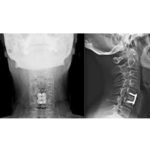

Anterior Cervical Discectomy and Fusion Surgical Technique

Courtesy: Dr Kshitij Chaudhary, Spine Surgeon, Sir HN Reliance Foundation Hospital, Mumbai